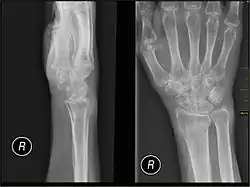

- Multizentrische karpotarsale Osteolyse mit oder ohne Nephropathie[7]